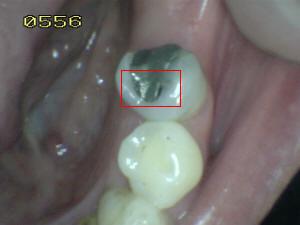

Sistema Internacional para la Detección y Evaluación de Caries (ICDAS)

¿Determine los códigos pertinentes a cada imagen?

Click en el hipervínculo: Para comparar el resultado de su diagnóstico